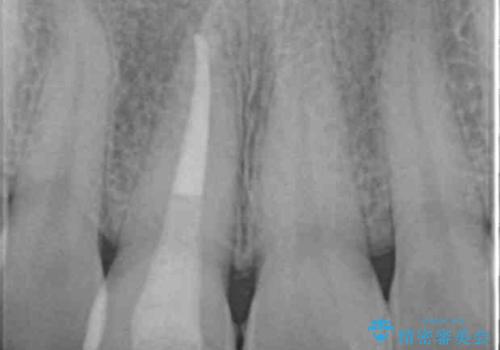

- 歯ぐきに、にきびのようなものができ治らない、と治療を希望され来院されました。

歯髄の検査、X線検査より神経の失活が確認されたので、根管治療・ファイバーコア築盛 ・ジルコニアクラウンの製作、と治療を進めます。